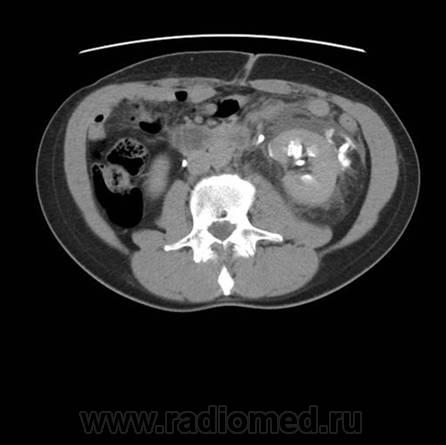

Травма. Боли в области поясницы.

Травматическое повреждение левой, по всей видимости, лоханки с разрывом и затеками контрастного препарата и мочи...